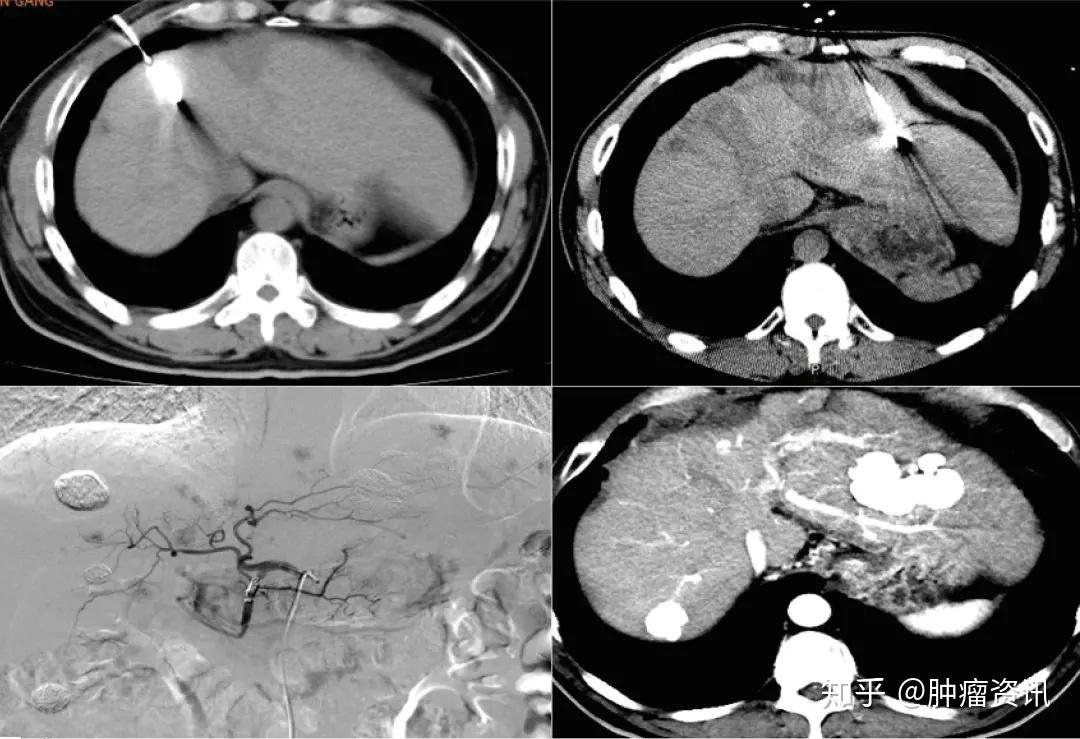

肝癌常症状无特异性,中晚期肝癌的症状则较多,常见的临床表现有肝区疼痛、腹胀、纳差、乏力、消瘦,进行性肝大或上腹部包块等;部分患者有低热、黄疸、腹泻、上消化道出血;肝癌破裂后出现急腹症表现等。也有症状不明显或仅表现为转移灶的症状。那么有助防治肝癌的方法是什么,我们一起来看一下。

2有助防治肝癌